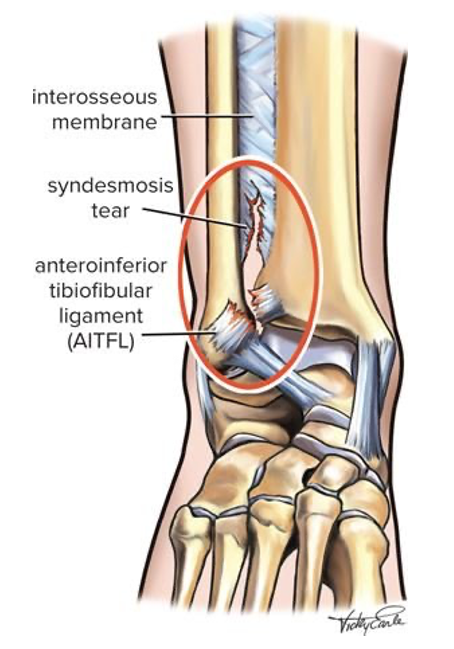

Lesão da sindesmose

A lesão da sindesmose do tornozelo, também conhecida como entorse alta do tornozelo, é uma condição incomum que afeta a estrutura fibrosa que conecta os ossos da tíbia e do perónio.

A lesão da sindesmose do tornozelo geralmente ocorre devido a uma força rotacional ou um trauma direto que provoca uma separação anormal entre a tíbia e o peróneo. Tipicamente, resultam de uma rotação externa forçada do pé com um tornozelo em dorsiflexão, como em desportos que envolvem mudanças rápidas de direção, como futebol, basquetebol, e rugby.

As lesões da sindesmose podem ser classificadas de acordo com a gravidade da lesão (número de ligamentos afetados), o grau de instabilidade do tornozelo e a diástase (separação) entre a tíbia e o peróneo nos exames de imagem.

• Lesão de Grau I (Leve): Estiramento ou rotura parcial dos ligamentos da sindesmose sem diástase entre a tíbia e o peróneo.

• Lesão de Grau II (Moderada): Rotura parcial com alguma diástase (na RMN e mas não no Rx), podendo haver sinais de instabilidade ou não, o que condiciona o tipo de tratamento.

• Lesão de Grau III (Grave): Rotura completa dos ligamentos da sindesmose com diástase clara entre a tíbia e a fíbula (já visível no Rx), resultando em instabilidade evidente do tornozelo.